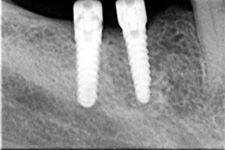

Velká mezera

Náhrada jednoho zubu pomocí implantátu je možná také v postranním úseku chrupu. Při ztrátě většího počtu zubů ve frontálním nebo postranním úseku může být mezer uzavřena větším počtem jednotlivých implantátů.

V případě chybění většího počtu zubů v postranních úsecích čelistí je možné ošetření pomocí implantátů, které nahradí ošetření pomocí snímacích náhrad kotvených na zbývajících zubech nebo patře.

Protetické řešení může být pomocí můstku, který je kotvený na implantátech nebo pomocí jednotlivých korunek na implantátech.